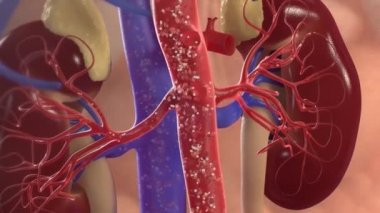

İnsanmikroSağlıkkanİlaçdikkatHastagövdeTedaviHastalıkbiyolojikanserbölümSistemAcıorgAyrıntılarkanaltaşlartüplerTeşhisanatomiBağışMikroskopfizyolojiNanoBöbreklerBöbrekİdrarfiltrasyonTümörmorfolojiiltihabımikroskopidonöriç organlara aitÜrogenitalÜrolojinefrithistolojiÜreböbreküstüDiyalizGlomeruluspiyelonefritnefronÜrologHematoksilenhydronephrosisurolithiasisBenzer İçerikler